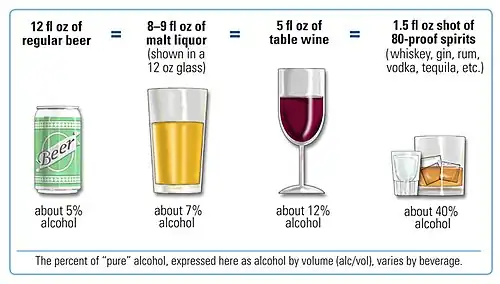

Lifestyle

Drinking alcoholic beverages increases the risk of breast cancer, even among very light drinkers (women drinking less than half of one alcoholic drink per day).[103] The risk is highest among heavy drinkers.[104] Globally, about one in ten cases of breast cancer is caused by women drinking alcoholic beverages.[104] Alcohol use is among the most common modifiable risk factors.[105]

Actions to prevent breast cancer include not drinking alcoholic beverages, maintaining a healthy body composition, avoiding smoking and eating healthy food. Combining all of these (leading the healthiest possible lifestyle) would make almost a quarter of breast cancer cases worldwide preventable.[116] The remaining three-quarters of breast cancer cases cannot be prevented through lifestyle changes.[116]